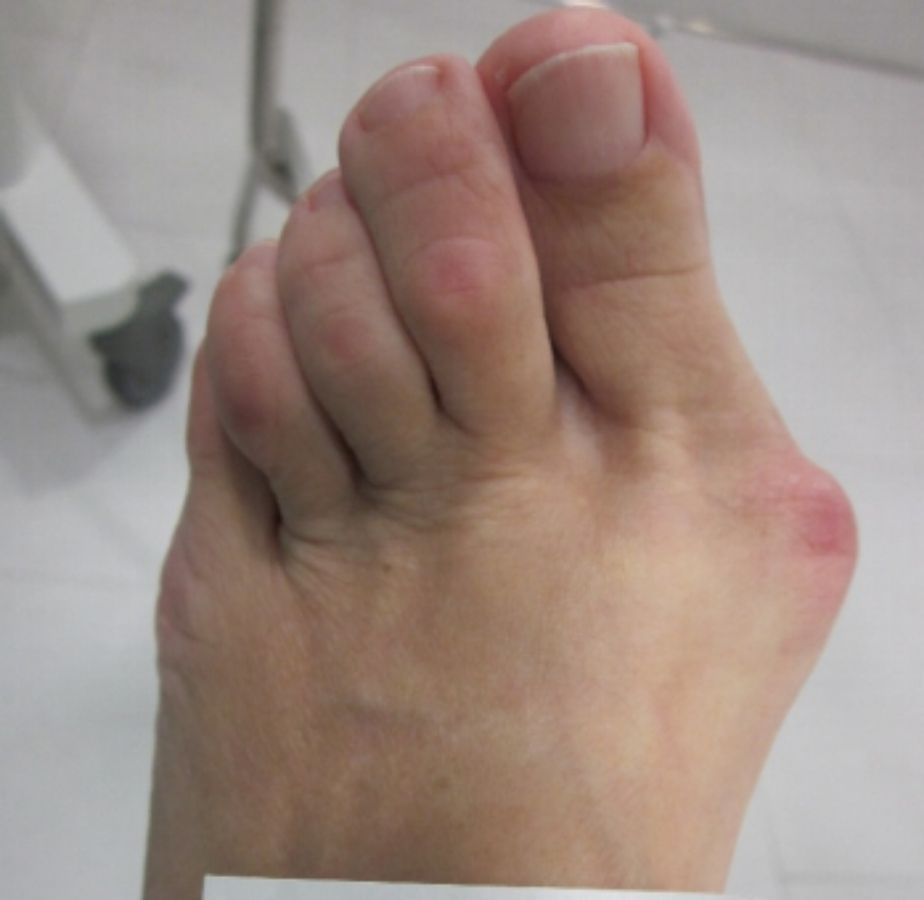

ANTES

casos reales juanetes alicante (2)